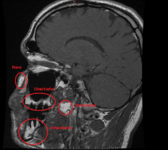

Ich habe auf Toxcenter endlich (aus dummen Zufall) die Bilder gefunden wo man Kieferaufnahmen erkennt, bewertet wurden, sowie auch Hirnaufnahmen.

https://web.archive.org/web/2014081...er.org/atlas-der-giftherde/index-bilder.php?0

Jetzt kann ich endlich versuchen mein OPG zu deuten. Ferner habe ich meinen Zahnarzt darum gebeten mir eine Überweisung zur Radiologie zu geben damit ich ein Vergleich des Kiefers vor und nach der Sanierung habe. Und auch um die aktuelle Belastung mit den Bildern und Dokumentationen von Toxcenter bewerten zu können. Oder es zumindest zu versuchen. Obs stimmt oder nicht wäre sowieso egal da sich an meiner Therapie nichts ändern wird. Das einzige wäre das sich Amalgamsplitter im Kiefer befinden. Die müssten dann operativ entfernt werden. In meinen Fall wären das 2 Zähne.

Weil ich Angst habe das mein Hirn von Schwermetalle geschädigt ist, und die Radiologie es nicht sieht ( weil die Microweiße Punkte im Hirn keiner Bedeutung zuweisen, diese sich aber über kurz oder Lang vergrößern können) habe ich die CD's der beiden MRT's aus den letzten beiden Jahren angefordert und möchte mittels Daunderers Bildmaterial mein Hirn mal vergleichen. Vielleicht erkenne ich ja Auffälligkeiten.

Um ein Microadenom auszuschließen erfolgt MRT 3 in den nächsten 4-8 Wochen. Dabei begleitet mich ein Neurologe der mir dann hoffentlich auch mal Diazepam verschreibt. Ich möchte das Zeug unbedingt testen und in wirklich schwierigen Zeiten so wie gestern und heute einfach mal 2 Tage nehmen um ne Pause von meinen Rückenproblemen zu haben. Plan sind 2-4 Einnahmezyklen pro Monat jeweils über 2 Tage um keine Abhängigkeit zu riskieren. Die Nebenwirkungen sind deutlich milder als bei Ortoton.